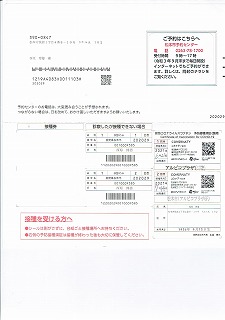

接種済証

接種説明書

③

② 3回目コロナワクチン接種 22.02.26

①1回目2回目コロナワクチン摂取済み票20210714=pdf

ワクチンパスポート=jpg

ワクチンパスポート個人情報削除=jpg

②  ①

①

高齢者肺炎球菌予防接種済証.jpg)